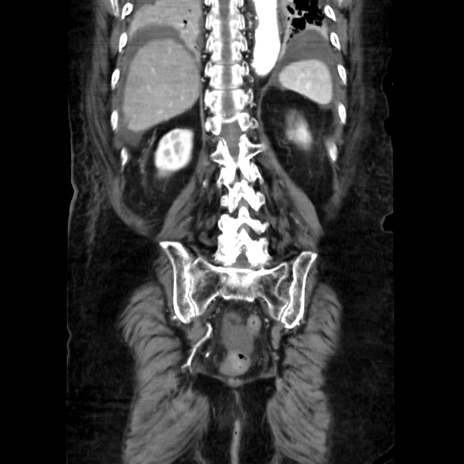

症例40(冠状断像)

【症例】90歳代女性

【主訴】腹痛・嘔吐

【現病歴】 食欲低下、嘔吐があり昨日他院受診。肺炎と診断され入院となる。入院後より腹部全体に圧痛あり。胃管留置され経過みていたが、症状持続するため、

当院転院となる。

【既往歴】胸椎圧迫骨折、胆石症

【身体所見】腹部:中央に激痛あり、圧痛あり、反跳痛不明

【データ】WBC 17100、CRP 18.82

冠状断像